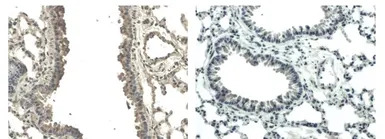

IHC-P analysis of lung tissue sections from LPS exposed mouse using GTX53099 VEGFB antibody [6E72].

Left : Primary antibody

Right : Negative control